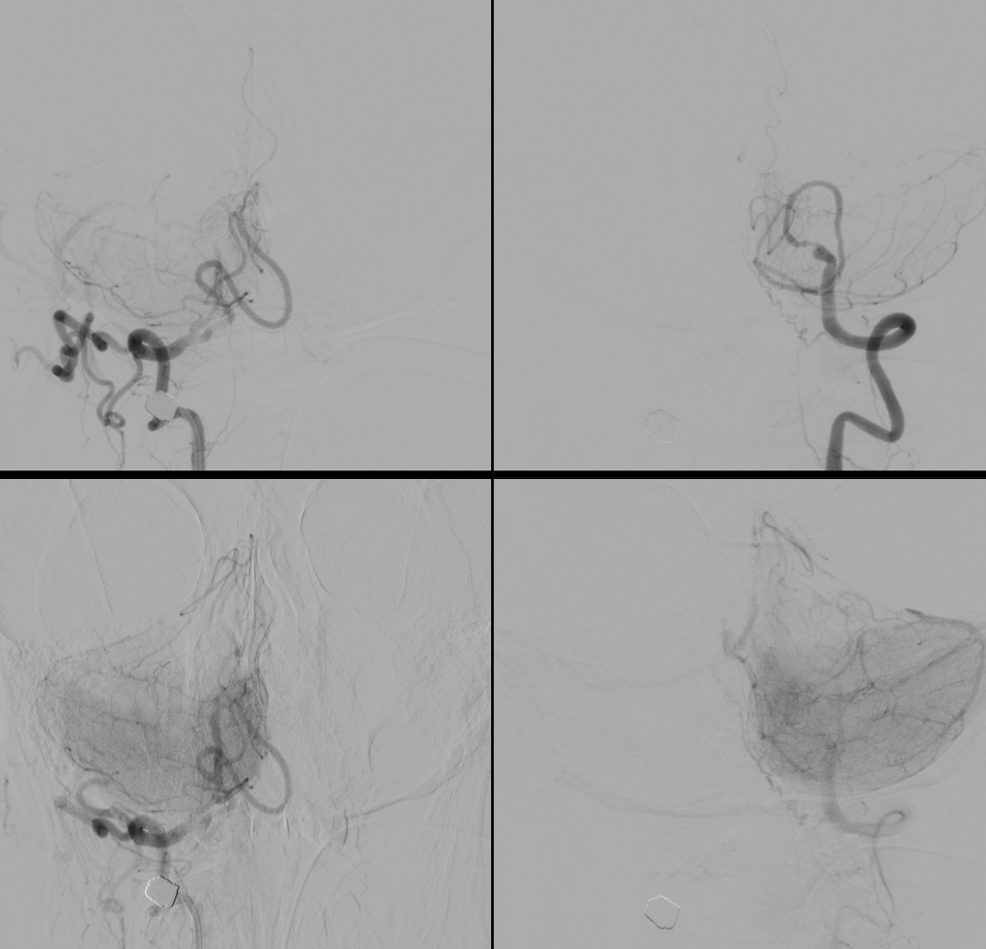

Atheromatous lesions often increase wall thickness, with various tissues present. The biology is beyond complex and certainly beyond the scope of what we are about. However, the thicker the wall, the more likely one is to see vasa vasorum. Here is a really nice case of that

History is progressive weakness

In faint blue we see the walls of the occluded part of the left vert (much larger than the right vert). Viewing the walls blue means that they are vascularized with the injection of the left vert (vasa vasorum). A mix of calcification and vasa vasorum is possible — see below. The basilar artery is almost white because it receives contrast with the injection of both vertebral arteries. Bone is also shades of grey.

Snapshots. The course of the closed vert shows that recanalization is better from the left.